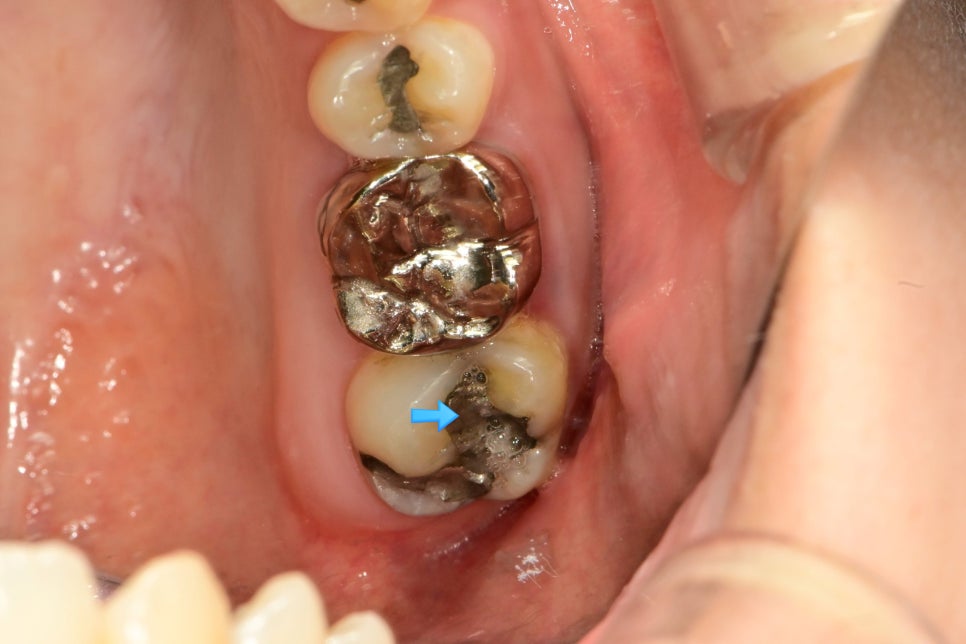

우측 구치부 근접 임상사진 — 아말감 경계 파절과 변색 부위에 화살표 표시

▲ 아말감 경계 파절·변색 — 이차 충치 의심 증례

치근단 X-ray — 아말감 하방 이차 우식 의심 부위에 파란 화살표 표시된 방사선 사진

▲ 방사선 사진으로 확인한 아말감 하방 이차 우식 — 육안으로 보이지 않는 충치도 X-ray로 확인 가능

이 치아의 경우 아말감은 겉으로 양호해 보이지만, 앞쪽으로 충치가 진행된 것을 확인할 수 있습니다.

두 치아의 대형 아말감 — 변연 파절과 균열이 화살표로 표시된 임상 사진

▲ 아말감 팽창으로 인한 치아 크랙(균열) — 위 치아는 팽창으로 크랙, 아래 치아는 아말감 파절 후 이차 충치 진행

이러한 상태의 아말감은 재치료가 적합하며, 증상과 환자분의 의사에 따라 인레이 또는 크라운 치료를 진행합니다. 아말감의 크기가 넓은 경우에는 인레이보다 크라운 치료가 더 적절한 선택입니다.